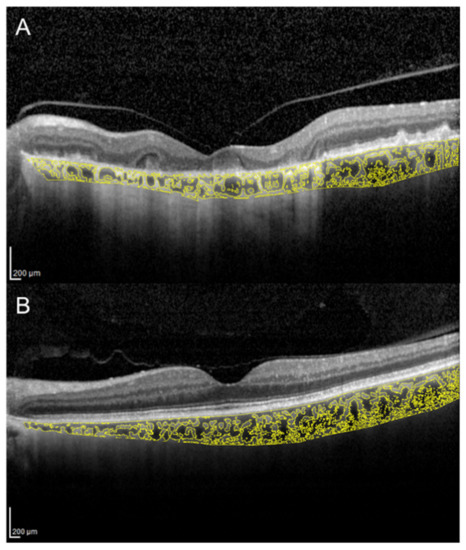

There is an ongoing debate as to whether the primary site of inflammation in multiple evanescent white dot syndrome (MEWDS) is the outer retina or the choriocapillaris. Increased CT and CVI were demonstrated in the acute stage of MEWDS, with subsequent reversal of choroidal changes along with outer retinal restoration and visual function recovery (Figure 2) [28]. This suggests an inflammatory involvement not only of the choriocapillaris, but also of medium and large choroidal vessels.

Figure 2. Choroidal vascularity index evaluation in a patient with multiple evanescent white dot syndrome. (A) In the acute stage, OCT shows ellipsoid zone disruption and a CVI of 69.3%. (B) In the healed stage, OCT shows normalization of the ellipsoid zone and a CVI decreased to 67.3%.

Nevertheless, it is still unclear if these choroidal changes play an active role in RPE/photoreceptor damage or are just a secondary effect of the inflammatory process occurring in the outer retina.